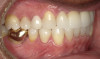

Fig 2. Candidates for hybrid teledentistry include patients with minor (Fig 2), moderate (Fig 3), and advanced crowding (Fig 4).

FIgure 2

Fig 3. Candidates for hybrid teledentistry include patients with minor (Fig 2), moderate (Fig 3), and advanced crowding (Fig 4).

Figure 3

Fig 4. Candidates for hybrid teledentistry include patients with minor (Fig 2), moderate (Fig 3), and advanced crowding (Fig 4).

Figure 4

The author's practice established a partnership with one of these disruptive clear aligner companies that offer this hybrid approach as a means of attracting consumers who were largely educated about the model and were seeking optimal results. The practice provides the initial case assessment and takes records to help the partner determine if the patient is a candidate for clear aligner treatment (Figure 2 through Figure 4), then it is compensated for these services. From this point on, the hybrid model involves teledentistry backed by state licensed dentists and orthodontists with minimal disruption to the practice. This, in itself, is a revenue builder, as it enables minimum aligner treatment cost to be paid with no additional fees or membership dues.